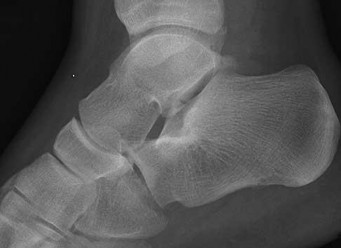

Figures 1a through 1c

Tarsal coalitions occur when primitive mesenchymal cells fail to differentiate and form the

normal articular separations between the tarsal bones of the hindfoot. Overall incidence is difficult to determine because many affected people are minimally symptomatic or asymptomatic. Symptomatic tarsal coalitions typically present in adolescents as a painful flatfoot; however, there are a number of possible presentations, and occasionally symptoms do not appear until adulthood. Most tarsal coalitions are between the calcaneus and the navicular (CN) and the talus and the calcaneus (TC). Although most TC coalitions are across the middle facet, posterior facet coalitions do occur. Plain radiographic evaluation of suspected tarsal coalition is the mainstay for diagnosis. However, coalitions can be bony or fibrous, and making the diagnosis can be difficult. The addition of CT images to distinguish bony definition and MR images to decipher soft tissue can aid in diagnostics. Bony coalitions appear as definite bony bridging between the bones, while fibrous coalitions are suspected when distortion of the bony anatomy is seen. Bony coalitions are best seen on the oblique view (CN) and Harris axial view (TC). There are a number of secondary signs such as the anteater (AE) sign (elongation of the anterior process of the calcaneus as it extends to the navicular as seen on the lateral view [CN]). talar beaking (traction spur of the talar neck thought to result from abnormal stresses as seen on the lateral view [both CN and TN]), and the “C” sign (a continuous cortical contour from the medial talus to the sustentaculum tali [ST]) as seen on the lateral view (TC). A number of newer signs are not as well known, such as a broad mediolateral dimension of the navicular on the anteroposterior (AP) view (the

navicular is wider than the talar head [CN]), nonvisualization of the middle facet on the lateral view (TC), the brick sign (a normal ST is flat, but a distorted ST is enlarged and curved [CN]), and a tapered lateral navicular bone as seen on the AP view (the medial navicular [CN] is much thicker than the lateral navicular).

Figure 1a shows talar beaking (TB), an AE, and an open middle facet (MF). Figure 1b shows a wide navicular (WN), and Figure 1c shows an abnormal articulation between the calcaneus and the navicular, all consistent with a CN coalition.